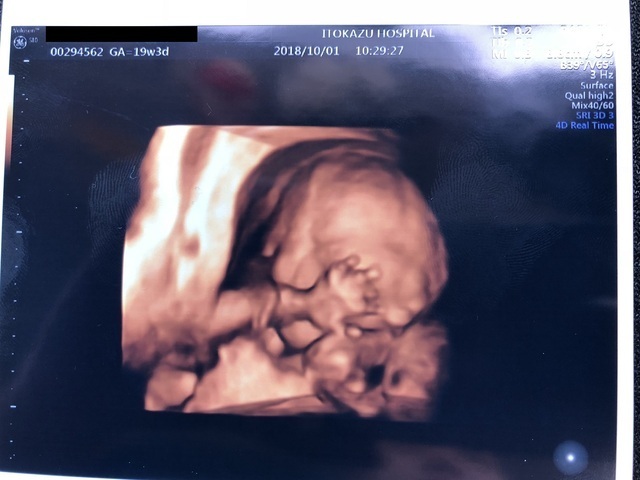

19週3日(19w3d・女の子)|てん1020 さん(26歳)

エコー写真撮影時のエピソード:

5月ごろのエコー写真です。顔見えるかなと期待していったら、エコーの画像の影響?でにっこり笑顔なお顔を見ることができました。

これを見た瞬間びっくりしたと同時に愛しくなりました。今は29週で、未だにはっきりと顔を見せてくれません。